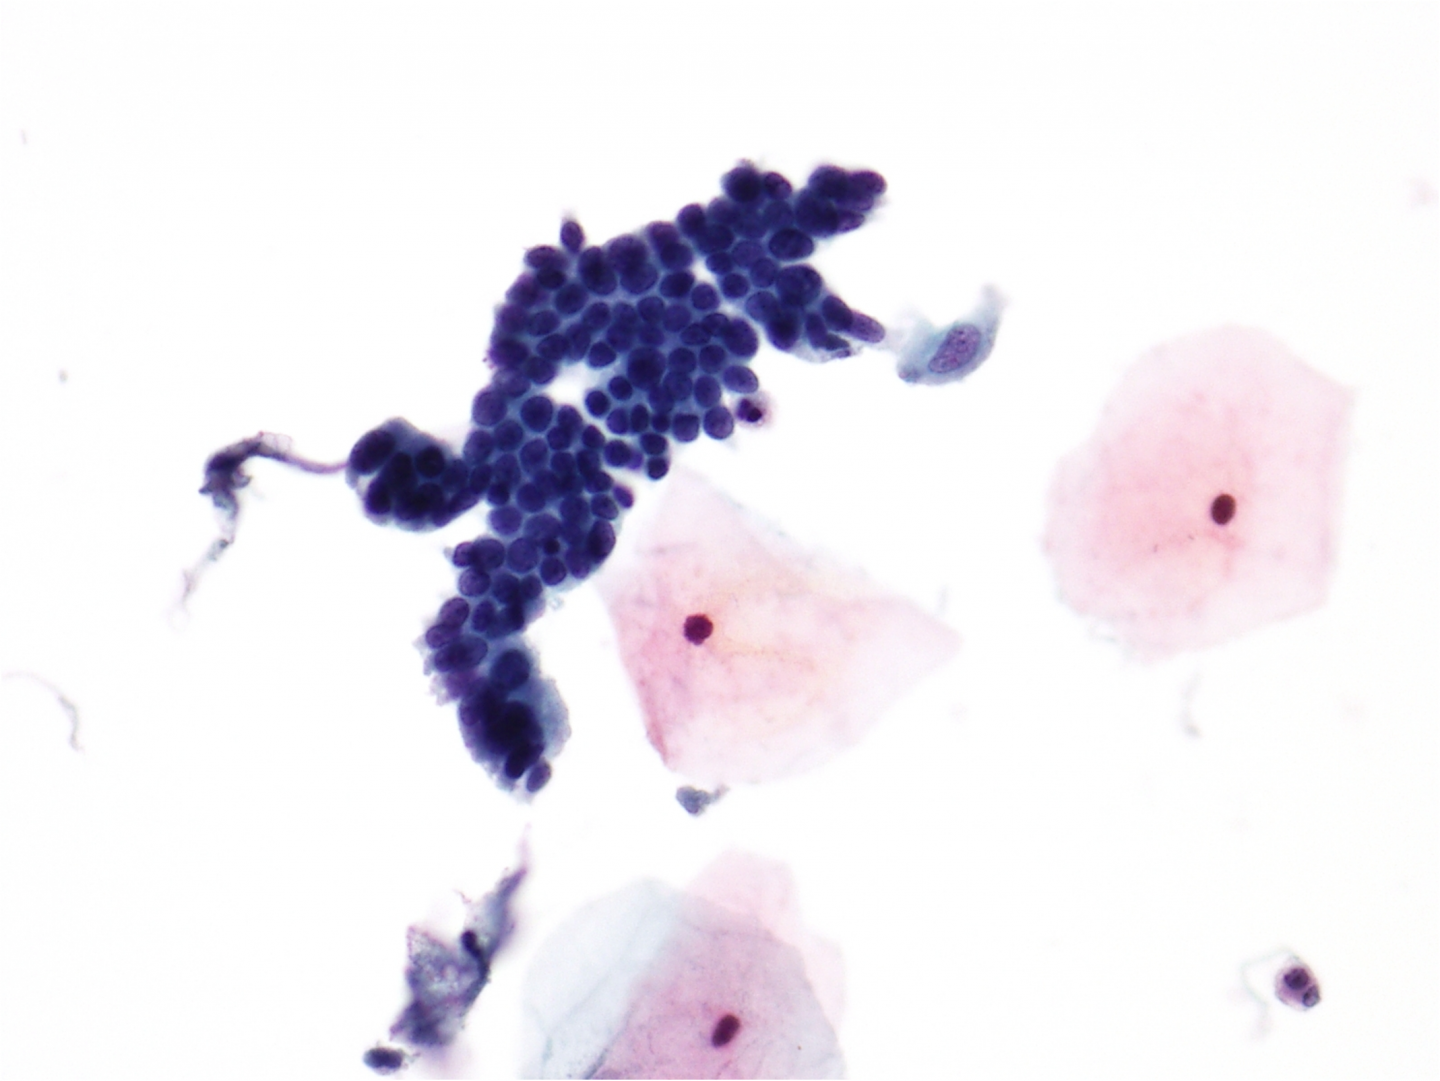

celule endocervicale prezente in analiza la nivelul microscopului